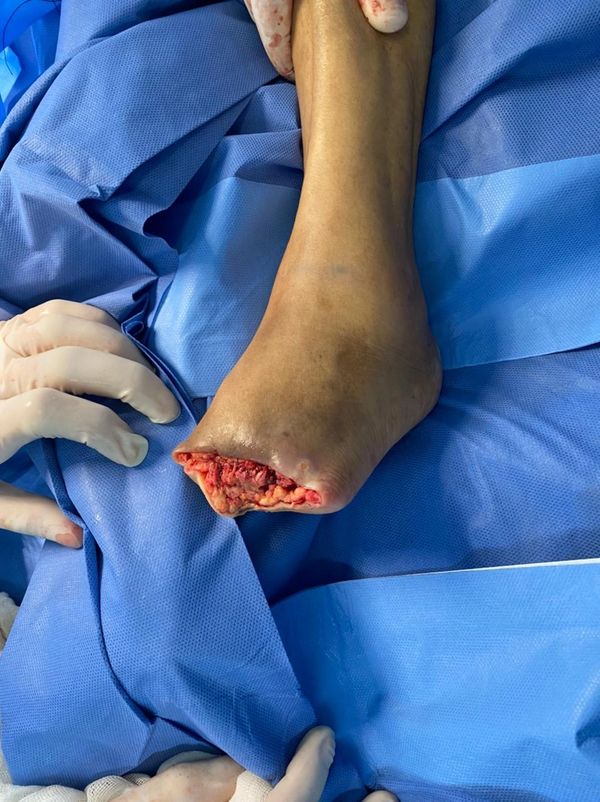

Angiólogos certificados, especialistas en el tratamiento de mínima invasión de la enfermedad venosa crónica (Várices ) , fleboestética , salvamento del pie diabético, manejo avanzado de heridas crónicas, Aneurismas , Fístulas Arteriovenosas y todo lo relacionado a los problemas de la circulación.